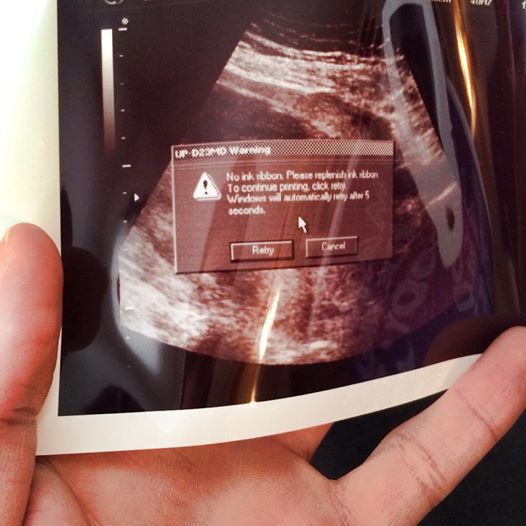

This is the first picture I was given of my unborn son

congratulations it’s a computer error